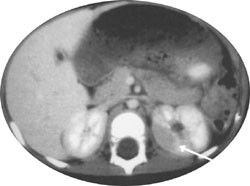

Pasient 3. 14 måneder gammel tidligere frisk pike ble innlagt i barneavdelingen med feberkrampeanfall etter at hun om morgenen hadde våknet med feber. Hun hadde forut for innleggelsen hatt noen dager med forkjølelse uten feber.

Ved innleggelsen ble det tatt urinprøver til videre undersøkelse med urinstiks, bakteriedyrking og mikroskopi. I urinen var det spor av blod og 2+ på leukocytter, men det kom ingen bakterievekst fra urinen, og mikroskopi ble oppfattet som normal. Det kom heller ingen vekst i blodkultur. CRP var ved innkomst 18 mg/l og steg i løpet av tre dager til 200 mg/l. Blodsukkernivå og elektrolytter var normale ved innkomst. Røntgen thorax var normal. Det ble første døgn startet med penicillin intravenøst pga. mistanke om luftveisinfeksjon, men på grunn av forverring ble det tatt CT-abdomen (fig 1), som viste fokale forandringer i venstre nyre, forenlig med akutt pyelonefritt. Det ble startet med cefotaksim intravenøst, som ble fortsatt i 14 dager. Under denne behandlingen hadde pasienten god bedring og kunne skrives ut i god allmenntilstand med trimetoprimprofylakse frem til miksjonsureterocystografi. I tiden frem til undersøkelsen hadde hun en urinveisinfeksjon med oppvekst av trimetoprimfølsomme Escherichia coli. EEG etter 14 dager viste intet sikkert patologisk.